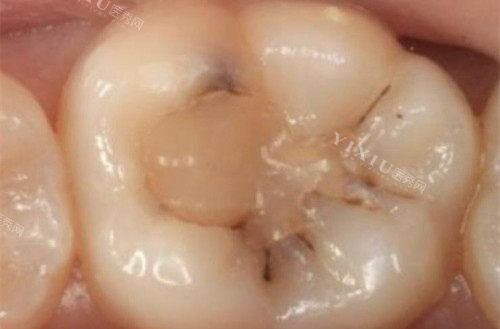

补牙的材料种类有很多,主要包括树脂、金属、陶瓷等。这些材料各有优缺点,适用于不同的牙齿缺损情况。树脂材料具有较好的美观度和粘附性,适用于前牙修复;金属材料具有较高的强度和耐磨性,适用于后牙修复;陶瓷材料则具有较好的美观度和生物相容性,适用于各种牙齿修复。